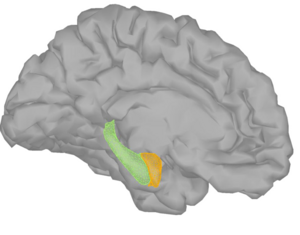

Publication: J Neurosurg. 2016 Jan 1:1-8. PMID: 26722859 Authors: Song F, Hou Y, Sun G, Chen X, Xu B, Huang JH, Zhang J. Institution: Department of Neurosurgery, People's Liberation Army General Hospital, Beijing, China. Background/Purpose: OBJECTIVE Preoperative determination of the facial nerve (FN) course is essential to preserving its function. Neither regular preoperative imaging examination nor intraoperative electrophysiological monitoring is able to determine the exact position of the FN. The diffusion tensor imaging-based fiber tracking (DTI-FT) technique has been widely used for the preoperative noninvasive visualization of the neural fasciculus in the white matter of brain. However, further studies are required to establish its role in the preoperative visualization of the FN in acoustic neuroma surgery. The object of this study is to evaluate the feasibility of using DTI-FT to visualize the FN. Methods Data from 15 patients with acoustic neuromas were collected using 3-T MRI. The visualized FN course and its position relative to the tumors were determined using DTI-FT with 3D Slicer software. The preoperative visualization results of FN tracking were verified using microscopic observation and electrophysiological monitoring during microsurgery. Results Preoperative visualization of the FN using DTI-FT was observed in 93.3% of the patients. However, in 92.9% of the patients, the FN visualization results were consistent with the actual surgery. CONCLUSIONS DTI-FT, in combination with intraoperative FN electrophysiological monitoring, demonstrated improved FN preservation in patients with acoustic neuroma. FN visualization mainly included the facial-vestibular nerve complex of the FN and vestibular nerve. |